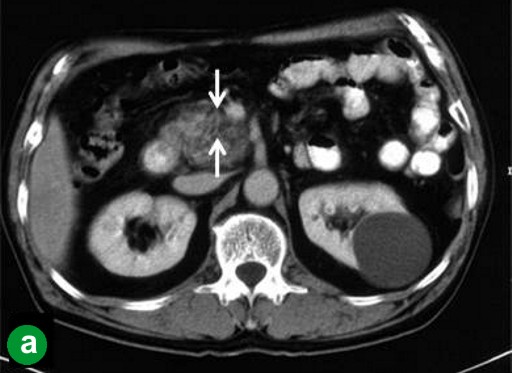

A 65-year-old man showed a dilatation of the main pancreatic duct on abdominal US at an annual medical checkup. An abdominal CT scan showed a 1 cm tumor in the head of the pancreas (Figure 1a), and dilatation of the main pancreatic duct in the distal part of the pancreas was demonstrated by MRCP (Figure 1b). A pylorus-preserving pancreaticoduodenectomy (PPPD) was performed in December 2000. The tumor was confirmed histopathologically to be a well-differentiated adenocarcinoma without lymph node metastasis (T1N0M0; R0; pathological stage: IA) (Figure 1c). Although the surgical margins were negative, pancreatic intraepithelial neoplasia was present in the resected pancreas. Adjuvant chemotherapy (4 cycles of 5-fluorouracil, leucovorin and mitomycin C given intravenously) was administered for 4 months. Periodic check-ups were performed thereafter.

Figure 1. Case#1: initial operation. a. A tumor approximately 1 cm in diameter was detected in the pancreatic head on abdominal CT (arrow). b. The main pancreatic duct was disrupted, and the main pancreatic duct of the distal pancreas was dilated on MRCP. c. Well-differentiated tubular carcinoma. Marked fibrosis and acinus atrophy were observed. Mild atypical cells with a slightly swollen nucleus formed an irregular ductal structure and invaded the parenchyma. (H&E stain, x100). |